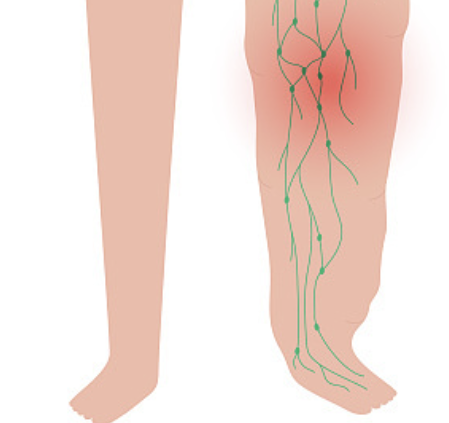

9. 림프절 종대

목, 겨드랑이, 사타구니 등에서 림프절이 붓고 커지는 증상이 나타날 수 있습니다. 이는 림프계에 백혈병이 영향을 미쳐 림프절 비대가 발생하는 것입니다.